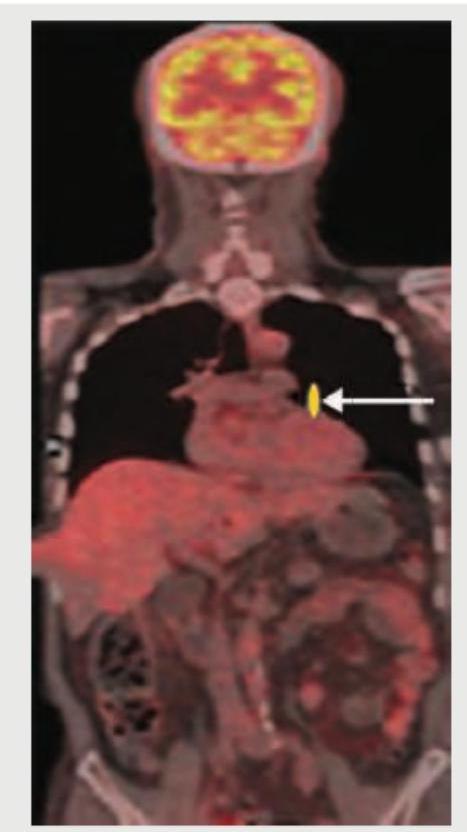

Explanation: ***PET-CT scan*** - The image displays a **fusion of anatomical detail** (like bone and organ outlines, typical of CT) and **metabolic activity** (represented by areas of increased tracer uptake, characteristic of PET). - The anatomical structures are visible in grayscale/darker tones, while areas of high metabolic activity (e.g., in the brain, heart, and liver) are shown in vivid colors (red, orange, yellow), indicating the combined nature of PET-CT. *PET scan* - A standalone PET scan would primarily show areas of **metabolic activity** and tracer uptake, but with significantly **less anatomical detail** and structural context compared to the image provided. - While it would show areas of high activity in colors, the underlying structural images (like rib cage, outline of organs) would be absent or very blurred. *MUGA scan* - A MUGA scan (Multi-Gated Acquisition scan) is used to assess **cardiac function** and primarily shows the heart chambers in motion to calculate ejection fraction. - The image provided is a whole-body scan, not focused on cardiac motion, and displays different imaging modalities. *HIDA scan* - A HIDA scan (Hepatobiliary Iminodiacetic Acid scan) is a nuclear medicine imaging test used to diagnose problems of the **liver, gallbladder, and bile ducts**. - This scan would exclusively show the hepatobiliary system and its function, which is not what is depicted in this comprehensive whole-body image.

Explanation: ***PET scan*** - The image displays a **whole-body imaging technique** with areas of increased **radiotracer uptake**, characteristic of **PET-CT (positron emission tomography) scans** using **FDG (fluorodeoxyglucose)**. - **FDG-PET-CT** is the **gold standard** for **staging and monitoring treatment response** in lymphomas, including NHL treated with RCHOP regimen. - It detects areas of **high metabolic activity** typical of viable tumor cells, and response is assessed using **Deauville criteria** or **Lugano classification**. - Post-treatment PET-CT helps differentiate between **residual viable tumor** and **fibrotic tissue**, which is crucial for management decisions. *HIDA scan* - A HIDA (hepatobiliary iminodiacetic acid) scan primarily evaluates the **hepatobiliary system** (gallbladder and bile ducts) for conditions like **acute cholecystitis** or bile duct obstruction. - It uses Tc-99m labeled radiopharmaceutical and does not produce a whole-body image with generalized metabolic uptake as shown. *MUGA scan* - A MUGA (multi-gated acquisition) scan is used to assess **cardiac function**, specifically the **left ventricular ejection fraction (LVEF)**. - It's often performed **before and during anthracycline therapy** (like doxorubicin in RCHOP) to monitor for cardiotoxicity. - It focuses on the heart and does not provide a whole-body metabolic assessment for tumor response. *Bone scintigraphy* - **Bone scintigraphy** (bone scan) uses Tc-99m MDP to visualize **bone metabolism** and detect fractures, infections, or skeletal metastases. - While it uses a radiotracer, the uptake pattern is limited to the skeletal system and shows **osteoblastic activity**, unlike PET-CT which shows soft tissue and nodal metabolic activity throughout the body.